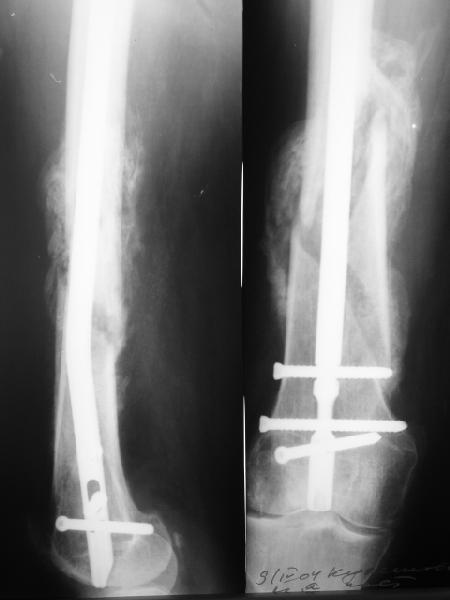

По прямой проекции неплохо. Что за стержень?

Антеградный остеосинтез при дистальных переломах бедра мы применяем давно, этот материал обобщен в канд. диссертации Александра Виноградского.

Предприятие ЦИТО выпускает доработанные нами гвозди, которые хорошо годятся для дистальных переломов, да и недороги. Можно вводть в дистальное овальное отверстие 3 винта, которые заклинивают друг друга.

Большеберцовые стержни отлично выполняют роль ретроградных бедренных. Конечно, которые не 9, а 12 мм в диаметре.

Примеры приложены.